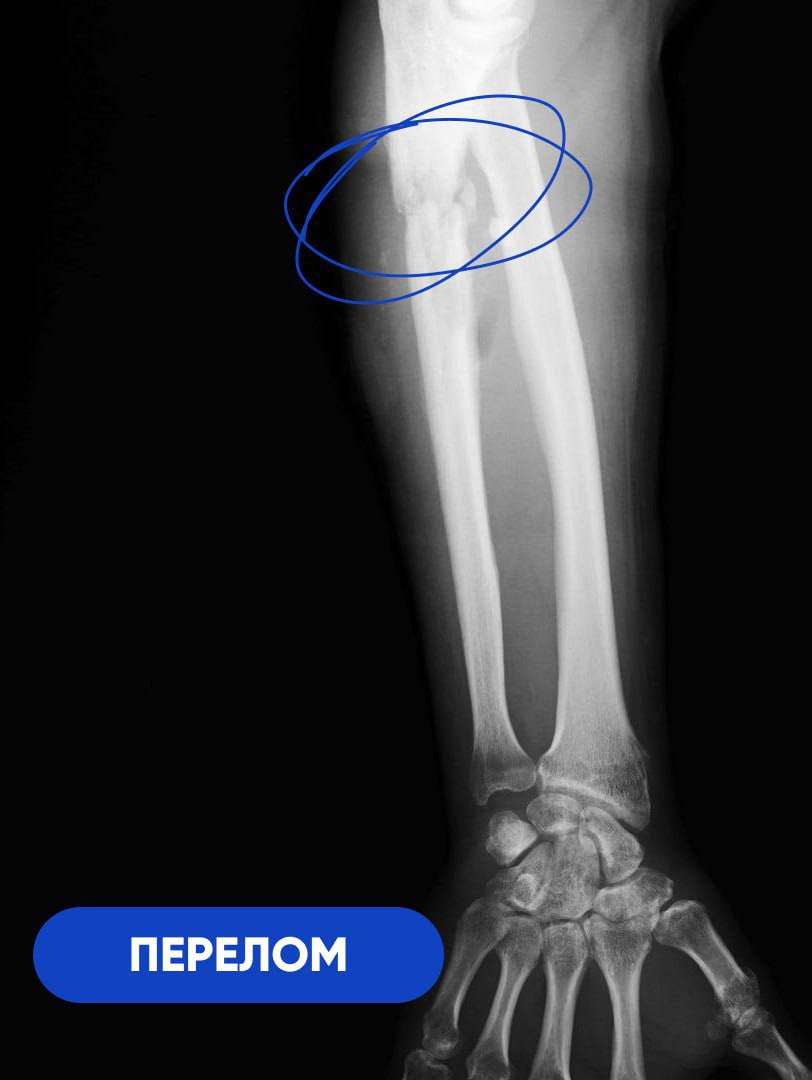

Несколько месяцев боли, гнойного воспаления и гипсовой иммобилизации. Результат – утратившая двигательные функции рука и ампутация в перспективе. К нашим травматологам-ортопедам 50-летний участник спецоперации обратился уже с тяжелой формой остеомиелита и большим костным дефектом. Лечение предстояло долгое и многоэтапное. Под руководством заведующего отделением травматологии и ортопедии №1 Сергея Глиняного был разработан четкий план действий, в том числе, на случай возможных осложнений.

-В первую очередь нам необходимо было справиться с инфекцией. При свищевом остеомиелите ждать результата от обычной антибактериальной терапии бессмысленно. Воспалительный процесс разрушил кость на участке длиной 8 сантиметров. Этот фрагмент подлежал удалению в пределах здоровых тканей. На его место установили спейсер из антибиотика и костного цемента. Мы изготовили его самостоятельно в условиях операционной, по собственной технологии и индивидуальным размерам. Имплантат выполнял двойную задачу. Во-первых, это источник антибиотика в непосредственном очаге заражения. Во-вторых,- механическая поддержка для кости за счёт своей армирующей функции, - объясняет Сергей Глиняный.